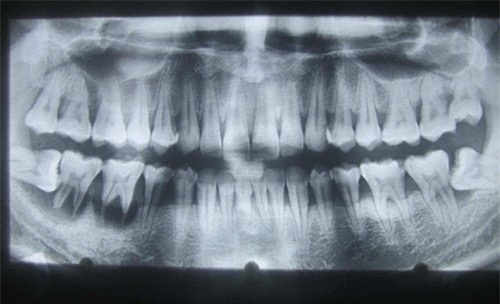

Răng 8 hàm dưới mọc lệch đâm ngang vào răng 7 gây tiêu xương ổ răng 2 răng này và phải nhổ bỏ |

Theo GS Hải, răng khôn mọc sau cùng trong khoảng thời gian từ 18-30 tuổi. Khoảng cách giữa răng số 7 và cạnh trong cùng của xương hàm sẽ quyết định vị trí răng khôn mọc như thế nào.

Nếu còn chỗ, răng khôn sẽ mọc thẳng bình thường, ít ảnh hưởng đến sức khỏe, nhưng khi thiếu chỗ sẽ không mọc hoặc mọc lệch, gây ra biến chứng đau đớn như viêm lợi, viêm quanh chân răng, sâu cổ răng, đặc biệt ở các răng khôn hàm dưới.